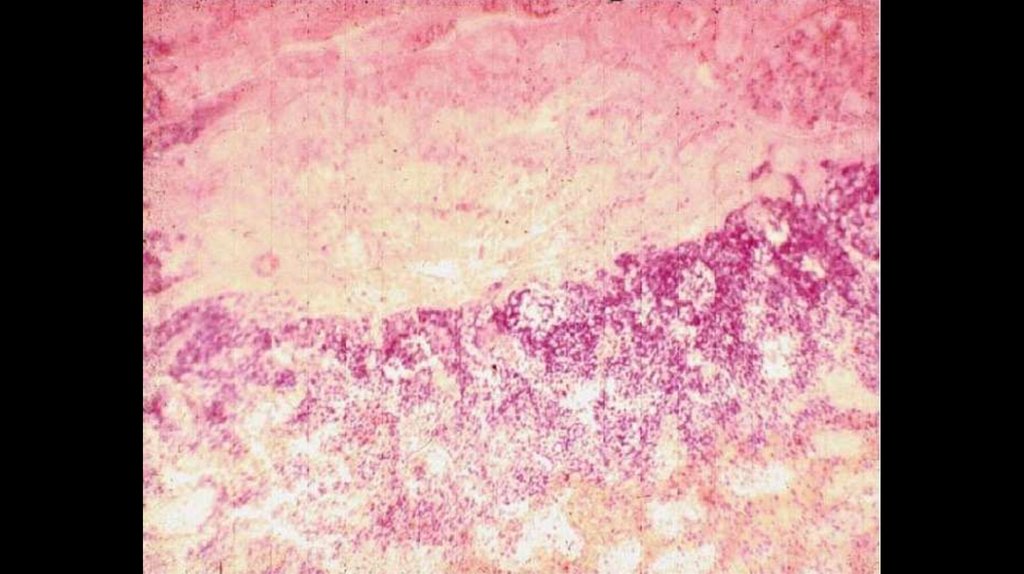

Гистология почек